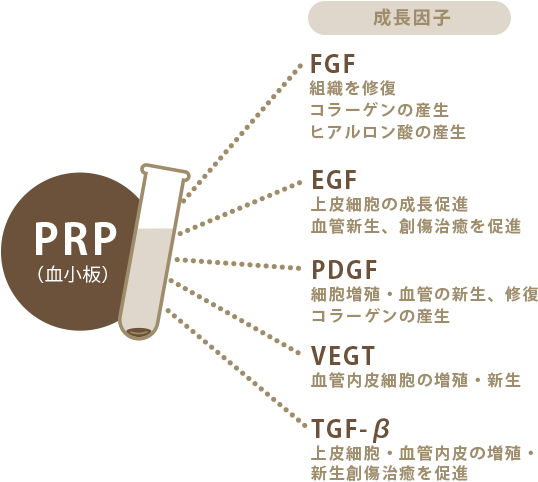

PRPには「成長因子」と呼ばれる体の細胞を蘇らせる成分が多く含まれています。肌の内部に注入すると成長因子が放出され、コラーゲンの生成や表皮の成長などが促され、シワの改善をサポートします。

PRPは血小板という細胞の中に、血管新生やコラーゲンの産生を促す沢山の因子を含んでいます。この治療の目的は患者様にこのPRPを投与することで皮膚の正常を改善することです。